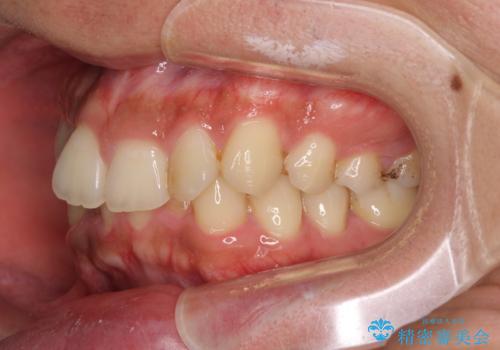

前歯のデコボコをスッキリ改善 インビザライン矯正

- 上下前歯のデコボコを気にして来院された患者様です。

全体的に叢生は軽度であったため、インビザラインにて矯正治療を行うこととしました。

デコボコの改善はもちろん、下顎前歯が隠れてしまうディープバイトも一緒に改善することができ、奥歯への負担を軽減することができました。